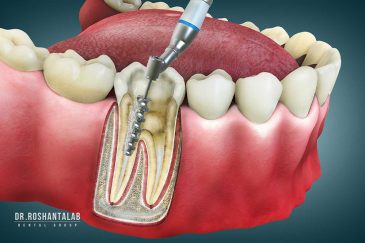

از عصب کشی و درمان ریشه دندان گرفته تا جراحی لثه و کشیدن دندان، تمامی مراحل توسط متخصص ترمیم دندان مدیریت میشود. ارائه باکیفیتترین خدمات ترمیم دندان برای سلامتی شماست.کاشت ایمپلنت فوری دندان